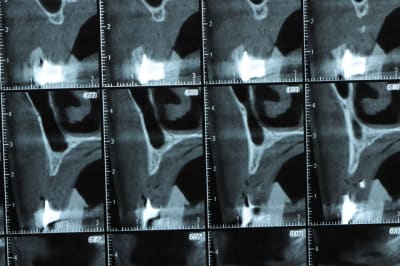

avant de faire la tomosynthèse je comprenais pas pourquoi j'avais aussi peu de contraste.

le patient ne souhaite pas, ou ne peut pas se faire poser 6 implants en haut, donc...overdenture sur 4. (si possible)

Ce n'est pas vraiment un consensus mais plutot du bon sens. Si tu as une crête en profil de lame de couteau cela signifie que tu as une fusion des corticales vestibulaire et palatine et donc absence de spongieux, ce qui comme tu le sais n'est pas indiqué en implanto (cj os de marbre par exemple)

Il me semble que Palti ou encore Szmukler-Moncler recommandent un minimum de 2-3mm. Si c'est plus fin, greffe d'apposition et GBR.

Dans ton cas il te faudrait abaisser la crête de 3 bons mm pour arriver à cette épaisseur.

Une petite étude de ton cas D57

Sous réserves bien sur de voir l’animal en vrai

Les zones exploitables radiologiquement parlant:

Coupes implant

2,3 40100

4,96 35130 avec sinus lift mais difficile

5,25 35150

6,02 35130

6,78 35115 après réduction de hauteur de crête

7,26 35115 après réduction de hauteur de crête

8,51 35150

10,43 40115 ou 50115

11,10 40115

Ce qui nous fait 9 implants possible évidement avec un comblement de sinus on augmenterait encore les zones implantable mais ce n’est pas le but recherché, avec 8 (4+4) il doit être possible de faire une belle barre support de complet